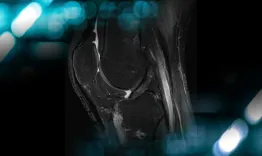

The goals of this clinical case are to discuss the physical examination of a multiligament knee injury and its surgical treatment.

Management of a chronic multiligament knee injury